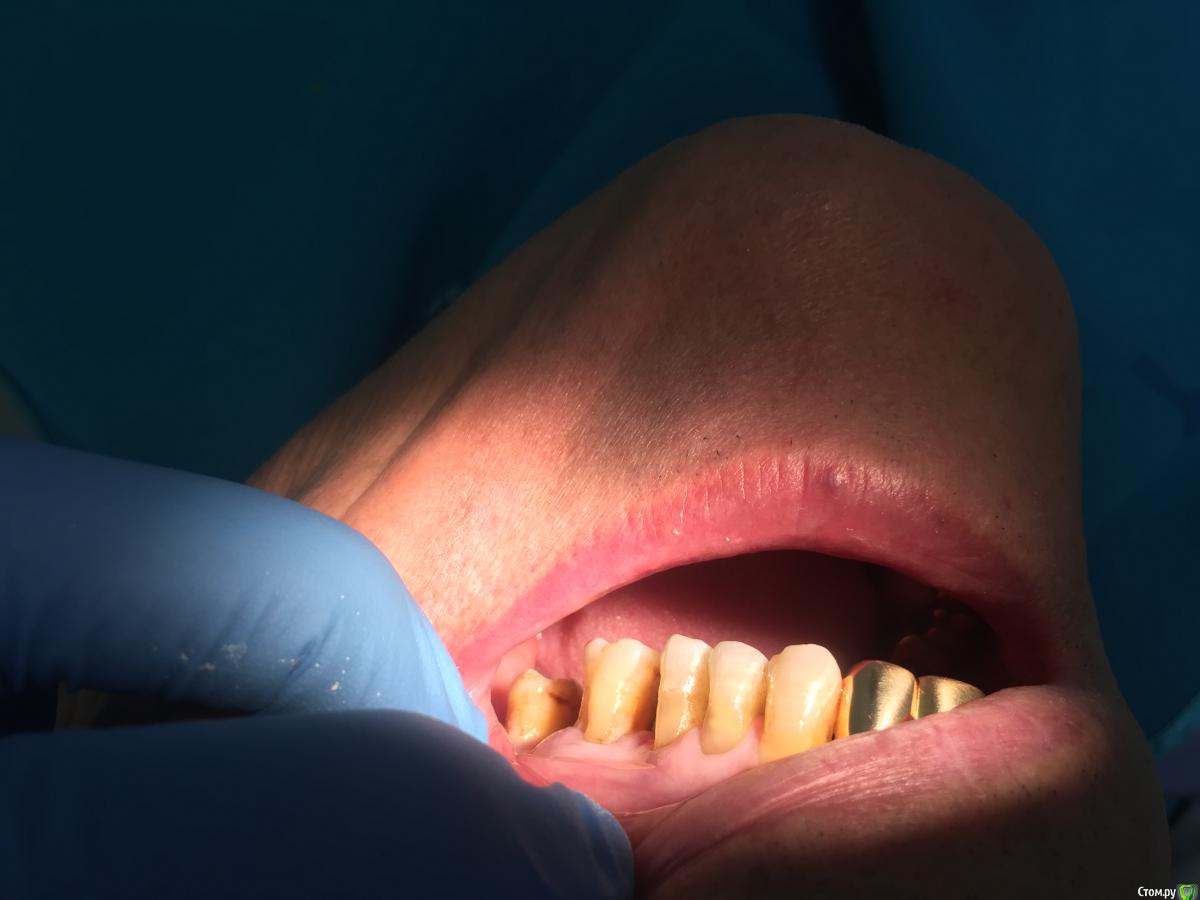

ravshanmax Опубликовано 3 января, 2017 Поделиться Опубликовано 3 января, 2017 Как лучше протезироват оголенных зубов? Посоветуйте пожалуйста.. Закрыть корня коронкой или не закрыть? Ссылка на комментарий

ravshanmax Опубликовано 3 января, 2017 Автор Поделиться Опубликовано 3 января, 2017 25, 26 зубы шатаются 2 степени. С 28 до 24 мк будет. Потом 23-13 тоже мк. Но как быть когда корни до бифуркации видны. Как обточить, до десны закрыт или нет? Посоветуйте пожалуйста. Ссылка на комментарий

dok1 Опубликовано 4 января, 2017 Поделиться Опубликовано 4 января, 2017 Фуркация наруже - ничего хорошего. Ссылка на комментарий

gum Опубликовано 5 января, 2017 Поделиться Опубликовано 5 января, 2017 Лучше их не протезировать, особенно 6, но если собрались, то препарируйте до десны, чтоб не углубляться в область фуркации и не травмировать десну, если есть карман, то покюретажить было бы неплохо Ссылка на комментарий

PLAY Опубликовано 6 января, 2017 Поделиться Опубликовано 6 января, 2017 такие зубы нельзя пилить до десны, усугубите дефект фуркации и сильно спилите зуб, от него ничего почти не останется. Ссылка на комментарий